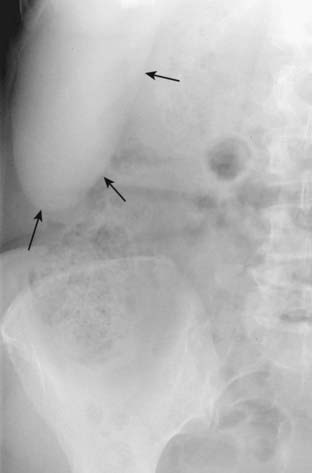

Figure 13-23 Position of the kidneys.

This is one image from an intravenous urogram (intravenous pyelogram [IVP]) in which the patient receives an intravenous injection of iodinated contrast which is excreted by the kidneys. Both kidney outlines (solid white arrows), ureters (solid black arrows) and urinary bladder (dotted black arrow) can be seen. Other images of the kidneys, including oblique views, were often obtained to visualize the entire contour of the kidney. CT scans and CT urograms have largely replaced IVPs. The liver (dotted white arrow) normally depresses the right kidney more inferior than the left kidney.

Figure 13-24 Enlarged kidney.

Soft tissue masses or organomegaly can be diagnosed from a conventional radiograph either by visualizing the edge of the mass if there is fat or air surrounding it or by displacement of bowel. A, On the conventional radiograph, there is a soft tissue mass in the left upper quadrant (solid white arrows), which is displacing bowel to the right (solid black arrow). B, A coronal reformatted CT scan of the same patient demonstrates a large renal cyst (solid white arrows) arising from the left kidney (solid black arrow), displacing it and the surrounding bowel. The cyst is compressing the spleen (S).